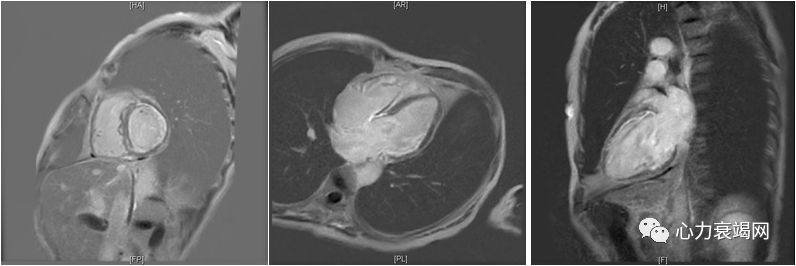

►平扫:左室及右心扩大(LA33mm,RA47mm,LV57mm,RV37mm),双室收缩功能减低,三尖瓣中量反流,LVEF 30%

►增强:心肌首过灌注室间隔壁内可见弧形早期充盈,延迟扫描室间隔近中段、前壁基底段肌壁间可见线样强化,左室游离壁可见心内膜下强化,左室乳头肌及侧壁肌小梁亦可见强化信号

►结论:考虑重症心肌炎可能性大,左右室壁充血水肿或纤维化改变